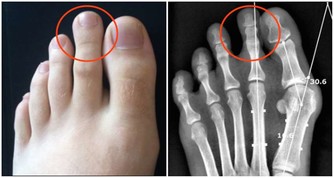

(圖片來源) 一位居住在倫敦的人的親身經歷 他去巴基斯坦開會的時候,突然胸口劇痛, 後來被醫院驗出來, 他的三條心血管已經被嚴重堵塞, 需要做搭橋手術。 手術的時間是一個月以後, 在這個期間,他去看一位治療師。 這位治療師給了他一個建議,結果卻十分驚人...! 食療一個月,心血管有驚人變化! 這位Hakim讓他自己在家中做食療,他吃了一個月。 一個月後他去同一家醫院做檢查, 發現三條血管幹乾淨凈, 原來堵塞的地方已經全通了。 為了讓更多的人受益, 他把自己的經驗放在網上分享, 他的前後兩張血管照片也放了在網上, 在照片中,服用食療之前與之後的分別, 連普通人也看得出來。